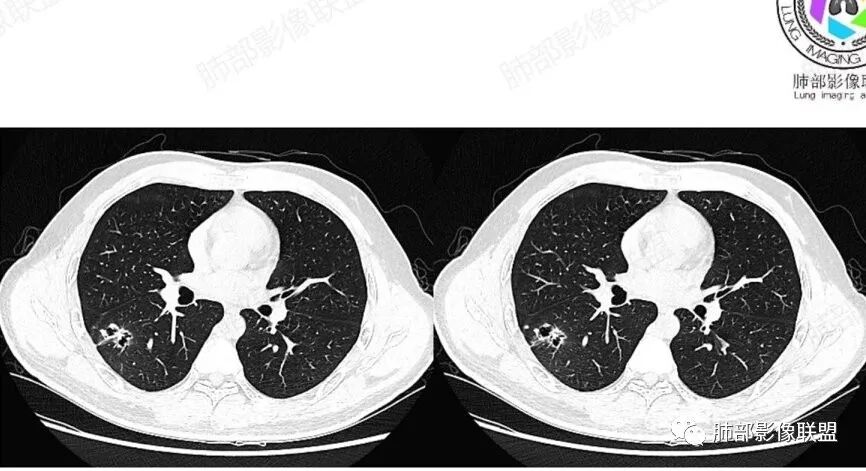

一切∮随缘:

左肺下叶空洞性病变,洞壁厚薄不均匀,洞壁似见小泡状低密度影,病变宽基底与与胸膜相连,周围伴有磨玻璃影,增强后可见壁强化,边界欠清,周围未见播散灶,左肺上叶纵隔胸膜下肺气囊,老年女性,主要是科室咳痰,咯血无发热,孤立性空洞性病变,考虑:腺癌(囊腔性肺癌),鉴别:隐球菌,放线菌,奴卡菌。

王开金江津中心医院呼吸科:老年女性,糖尿病,咳嗽,咳痰,痰血,无发热,血分析正常,左下叶背段空洞,周围光滑,内有洞丝,壁结节,无卫星灶,考虑肺癌,鉴别结核。

穿越七海的风:老年女性,糖尿病,咳血,左肺下叶空洞性病变,壁薄光滑,空洞内丝状物,壁结节无强化,周围有晕,考虑真菌感染毛霉?鉴别肺腺癌。

丽:老年女性,左肺下叶胸膜下空洞性病变,薄壁,边缘模糊有晕,空洞内不干净,丝丝缕缕,增强后洞壁有强化,有糖尿病病史,考虑感染性病变,毛霉?曲霉?

大雄:左下叶孤立空洞,病灶整体较僵硬,壁厚薄不均,无明显卫星灶,局部强化,倾向囊腔型肺癌。

徐飞:老年女性,咳血,糖尿病,左肺下叶囊腔性病变,内见少许分隔,增强后见部分壁不规则增厚及轻中度强化,纵隔多发肿大淋巴结,考虑囊腔型腺癌,鉴别毛霉菌感染。

必有路:肿瘤指标阴,胃肠道的转移基本不考虑,周围实际上比较干净,感染类的,不符   老年人   毛霉菌往往要有酮症基础,所以,囊腔肺癌>真菌(毛霉)